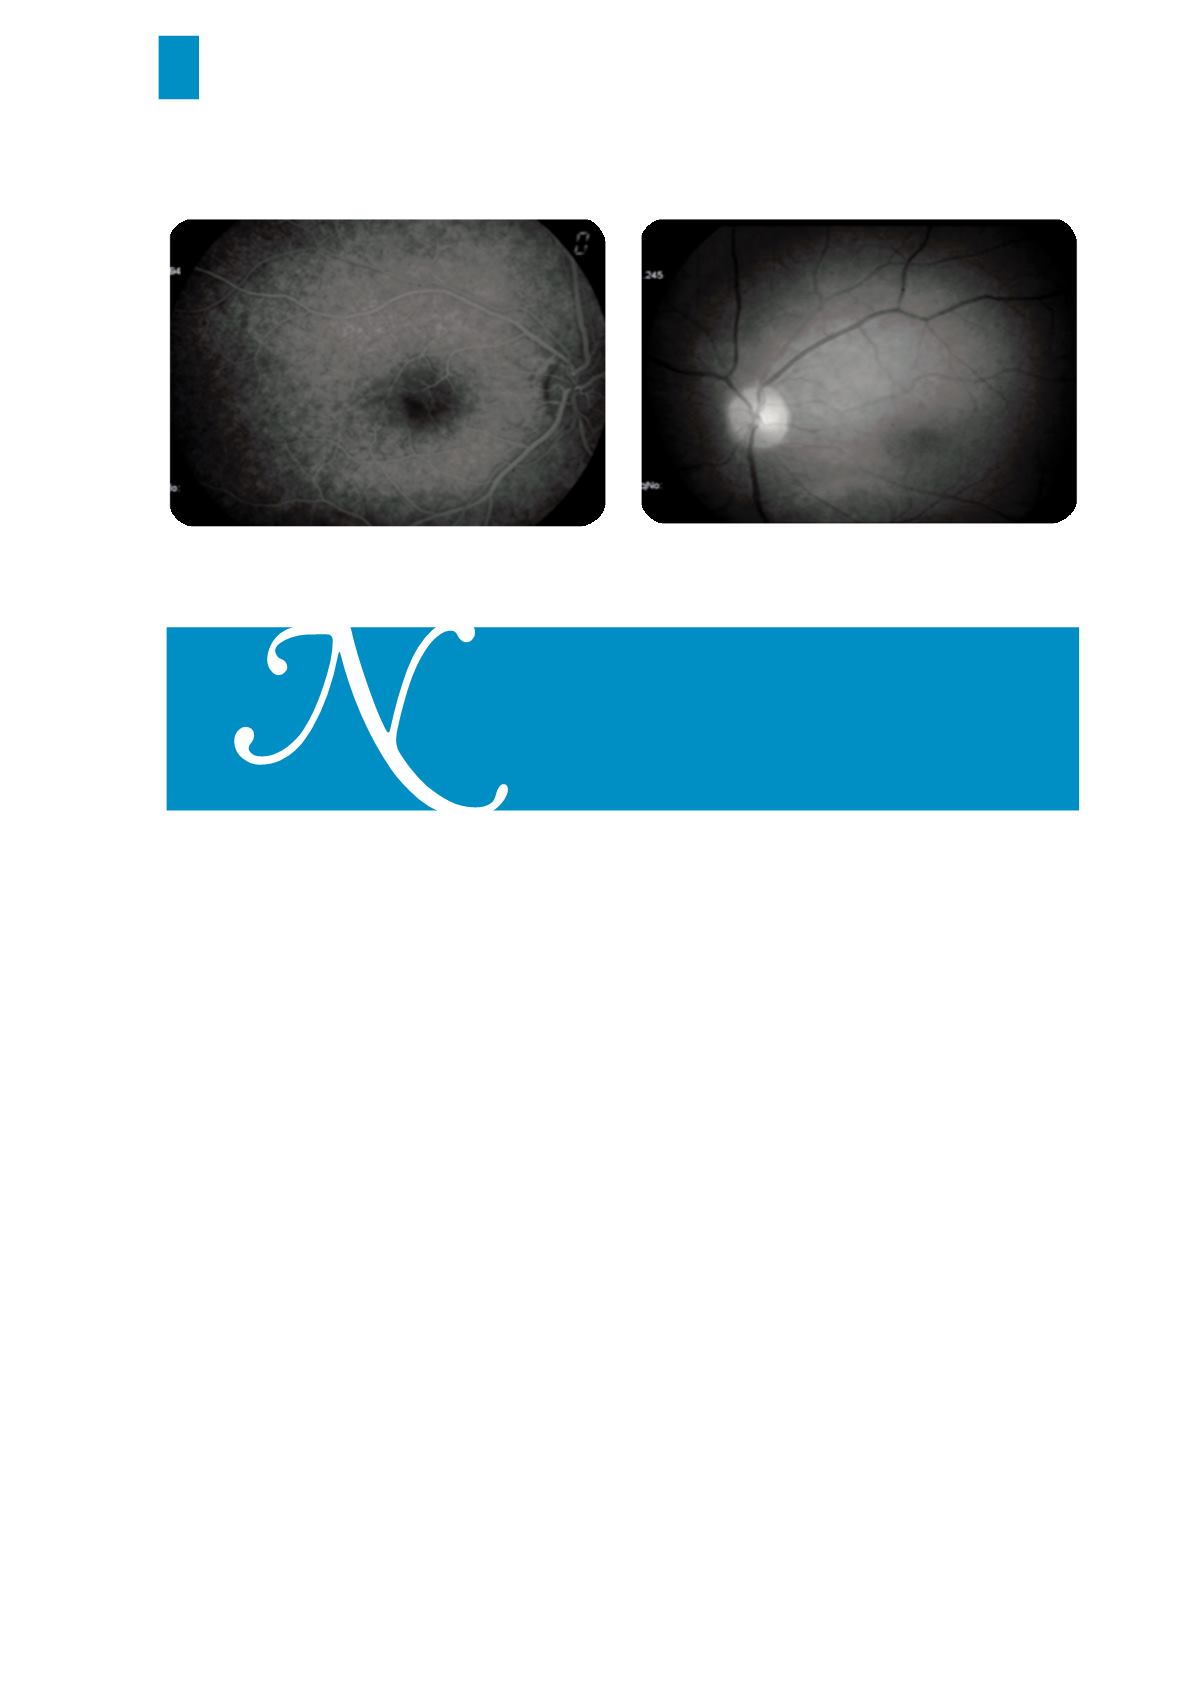

Fig. n.22 Neurite óptica retrobulbar (AF)

Fig. n.23 Neurite óptica retrobulbar (anerítica)